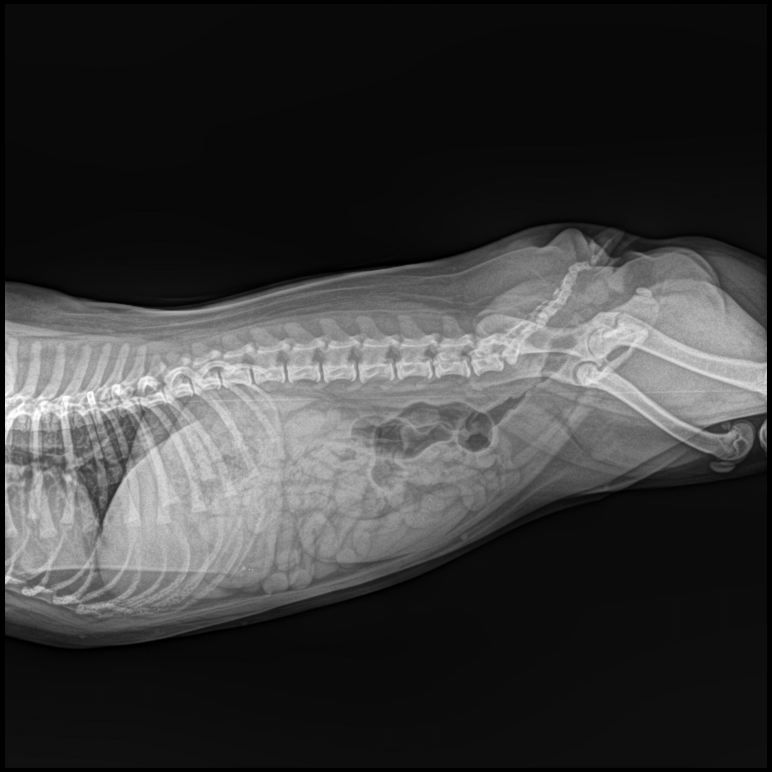

辐射剂量:宠物X光机一般为5KW的便携式X光机,采用高频高压发生器,功率相对较小,因此对身体伤害也相对较小。然而,任何X光检查都涉及一定量的辐射,尽管这种辐射剂量通常远低于对人体造成伤害的阈值。 检查必要性:X光片在诊断小猫的骨折、肺部炎症、膀胱结石等方面具有不可替代的作用。在必要时进行X光检查,对于确诊疾病和制定治疗方案至关重要。 频率控制:虽然单次X光检查对小猫的影响有限,但频繁进行此类检查可能会累积辐射剂量,从而增加潜在风险。因此,建议仅在必要时进行X光检查,避免不必要的辐射暴露。 山东十大体育投注网站有限公司是一家X光机生产企业,如果您正需要一台这样的设备可以致电联系我们。 Tel:18953679166 上一篇:医用X光机使用的高压电缆 下一篇:散乱射线的影响因素和消除办法